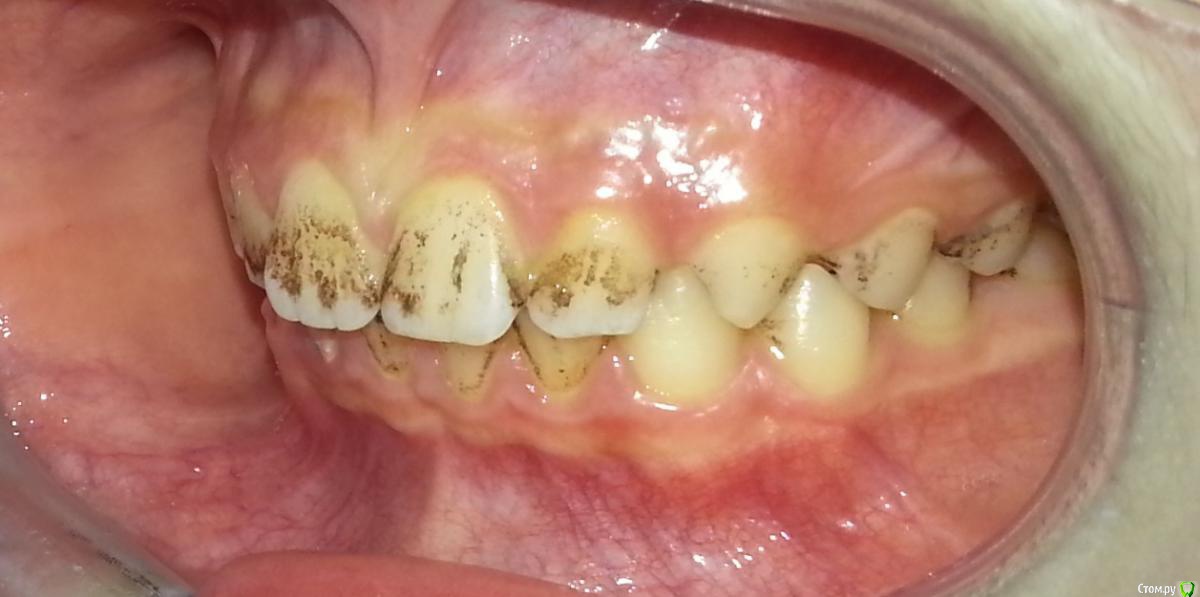

Nitrino1 Опубликовано 6 февраля, 2017 Поделиться Опубликовано 6 февраля, 2017 Здравствуйте коллеги, помогите с уточнением диагноза) Я не детский стоматолог, мамаша принесла ребенка заодно проконсультировать по поводу налета, посмотрел сфоткал) Первое что пришло на ум это налет Пристли)) Хотел уточнить) Жалоб нет, только эстетика..Убирали налет у стоматолога, через месяц все заново появилось.Буду благодарен если уточните как добиться постоянного эффекта.Ребенку 10 лет, мальчик Ссылка на комментарий

Nitrino1 Опубликовано 7 февраля, 2017 Автор Поделиться Опубликовано 7 февраля, 2017 @БендерПроблемы с желудком, когда пьет газировку его тошнит, это меня насторожило Ссылка на комментарий

krokomot Опубликовано 7 февраля, 2017 Поделиться Опубликовано 7 февраля, 2017 Тут реально просто грязища, если налет убирается стоматологом, то вполне домашней ежедневной и двукратной возможно предотвратить его образование. Вы лучше спросите сколько раз в неделю они чистят зубы? 2 Ссылка на комментарий